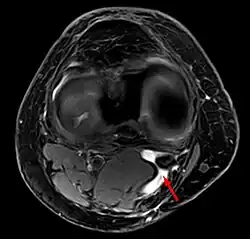

Diagnosis is by examination. A Baker's cyst is easier to see from behind with the patient standing with knees fully extended. It is most easily palpated (felt) with the knee partially flexed. Diagnosis is confirmed by ultrasonography, although if needed and there is no suspicion of a popliteal artery aneurysm then aspiration of synovial fluid from the cyst may be undertaken with care. An MRI image can reveal presence of a Baker's cyst.